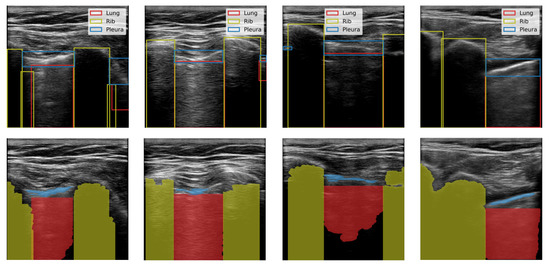

We produced binary semantic segmentation masks for the objects of interest by applying several computer vision algorithms to the areas delimited by the bounding boxes, see Figure 2. We assumed that the objects of interest differed from other objects in the bounding box by brightness. To create the segmentation mask for the lung class, we applied intensity thresholding in the bounding box with a threshold value determined by Otsu’s method. The initial result was refined by morphological dilation, and the holes in the mask were filled. Finally, the mask was returned to the coordinate system of the image. We repeated this process for each bounding box in an image. In the end, we kept only the largest contiguous region because some of the images contained multiple separate regions of the lung. We generated pleura masks using the same process. Similarly, masks were created for the rib class however, we inverted the mask produced by Otsu’s method and kept two separate regions.

Figure 2. Creation of semantic masks for the pleura, lung, and rib from labelled data. Top: Bounding boxes labelled by volunteers. Bottom: Semantic masks generated from the bounding boxes.